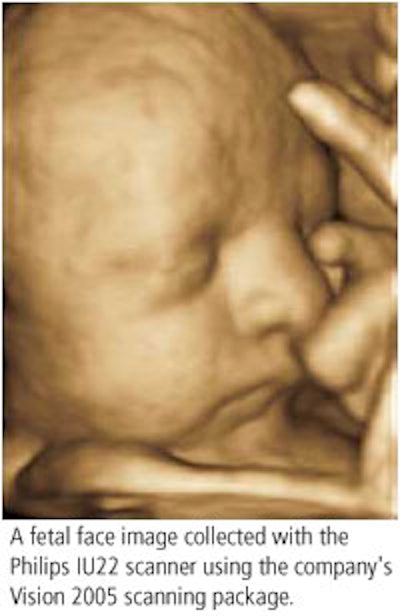

Philips Medical Systems of Andover, MA, will roll out several ultrasound systems and various new technologies in its product line, including enhancements to its flagship iU22 scanner and updates for the HD11 system.

Among Philips' ancillary product highlights will be the X3-1 xMatrix array transducer for real-time 4D volume-rendered imaging for general and cardiac applications, the new S5-1 transducer, and 3D Viewer, which allows physicians to review, display, and rotate 3D datasets and create multiplanar reconstruction views similar to those used in MR and CT.